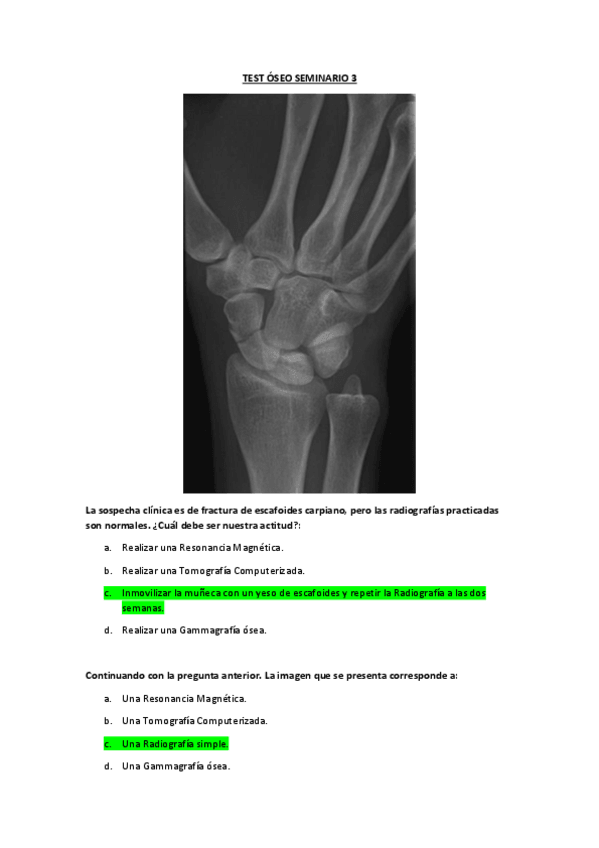

He publicado nuevos apuntes de 3º Radiología y Medicina Física. Protección Radiológica: seminario-3-radio.pdf

pdf